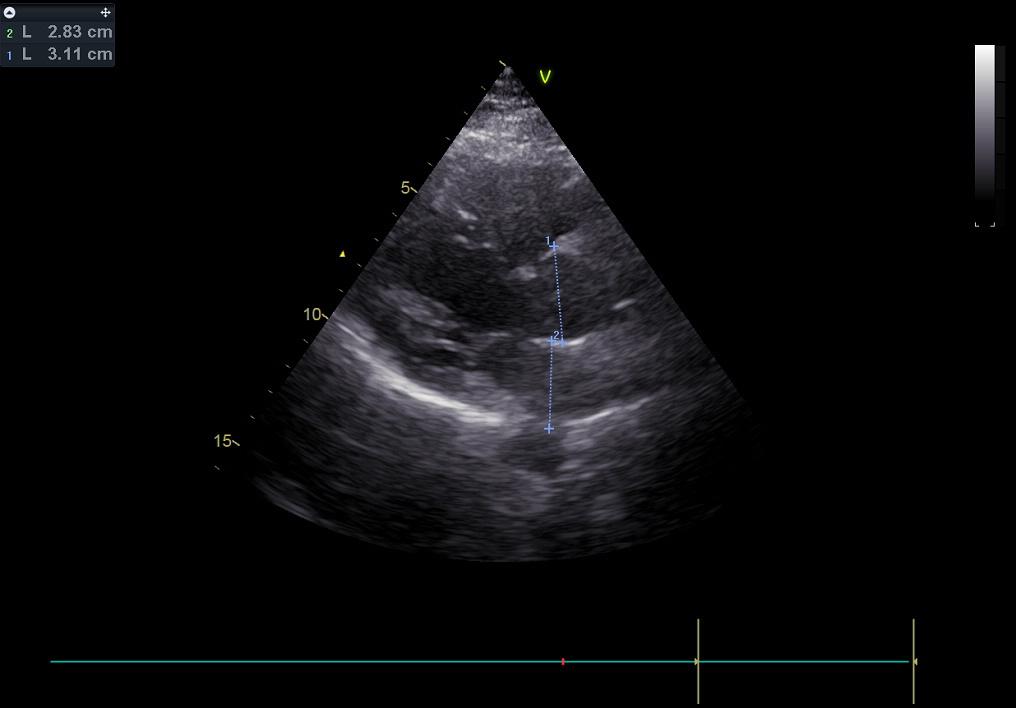

Before starting chemotherapy, we needed to make sure my heart was healthy enough to endure it. So I went to the hospital for a full cardiological exam: an electrocardiogram followed by an echography. We didn’t expect anything to show up - I have never suffered from cardiological issues - but basically, like with everything, “you never know”.

The data for this day are an electrocardiogram on the usual pink paper, and an echocardiogram, which is used to highlight the structure, function, and blood flow of the heart. The second image shows a color flow doppler, with in blue the blood that flows from the probe and in red the blood that flows towards it. Everything was healthy and ready to sustain chemotherapy.